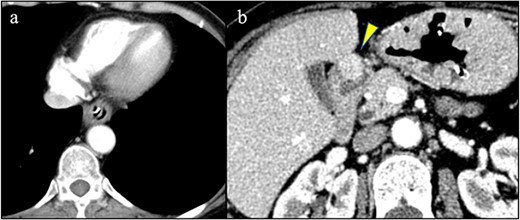

A 58-year-old woman with severe stricture of the lower esophagus was referred to our institution. She had been receiving medication to treat GERD at multiple facilities for the past 5 years. Six months prior to the referral, she underwent laparoscopic esophageal repair for esophageal rupture (Fig. 1a). After the rupture, she eventually presented with NE (Fig. 1b), a condition that consequently led to severe stenosis of the lower esophagus (Fig. 2). Multiple biopsies did not confirm any malignancy in the esophagus, and endoscopic balloon dilatation temporarily enabled endoscopic observation of the gastro-duodenum, which had no significant abnormal findings, but failed to relieve the constriction. Computed tomography revealed a 10-mm hypervascular mass on the anterior wall of the duodenum, suggestive of a gastrointestinal stromal tumor (Fig. 3); there were no findings suggestive of esophageal malignancy. Pathological diagnosis of the duodenal mass could not be determined because the endoscope used for endoscopic ultrasound-fine needle aspiration could not pass through the esophageal stricture.

Previous conditions of the esophagus. Esophageal rupture accompanied by a massive mediastinal abscess (arrowheads). Necrotizing esophagitis of the lower esophagus.